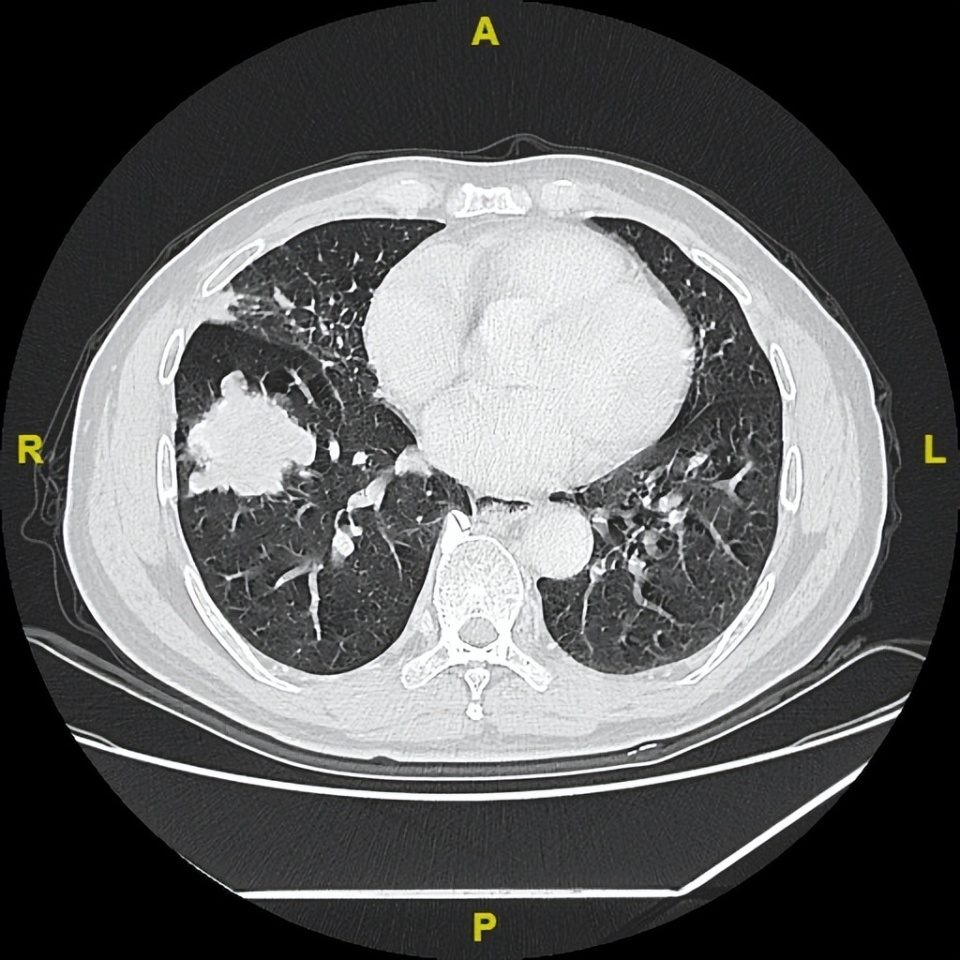

2024年2月19日

△治疗后不同随访时间的胸部及髋关节CT病灶变化